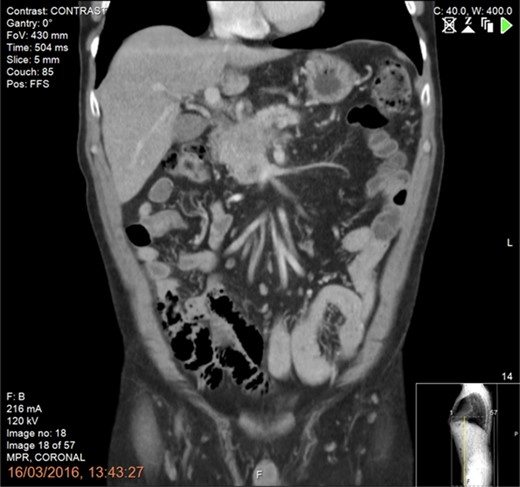

Following tissue confirmation, the patient was treated with neoadjuvant chemotherapy including 12 cycles of FOLFIRINOX. Re-staging CT scan showed good response with a recanalized portal vein without any evidence of vascular involvement or distant metastasis (Fig. 2). The patient was then offered a pancreaticoduodenectomy (PD) with simultaneous intraoperative IRE margin accentuation.

Preoperative CT scan of the abdomen and pelvis (portal phase) showing good response following neoadjuvant chemotherapy with recanalization of the portal vein and no evidence of vascular involvement or distant metastasis.